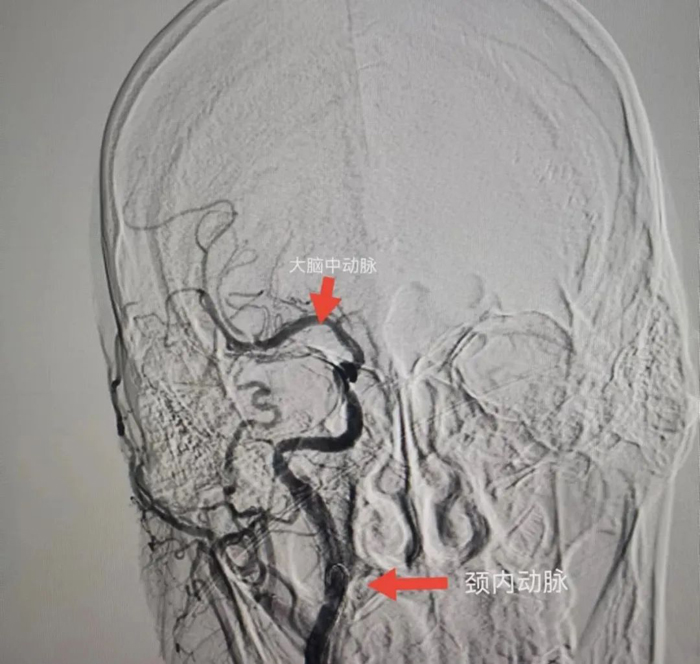

與患者女兒溝通,征得患者女兒同意后,立刻聯(lián)系CT室,半小時內(nèi)完成CT檢查,證實患者右側(cè)頸內(nèi)動脈和右側(cè)大腦中動脈閉塞,存在70毫升的缺血腦組織,有取栓適應癥。再次和患者女兒溝通,患者女兒接受風險簽字手術(shù)。立刻聯(lián)系介入室和麻醉科,一個半小時完成手術(shù)。

術(shù)中給予患者右側(cè)頸內(nèi)動脈植入支架和右側(cè)大腦中動脈取栓,患者血管達到3級再通。術(shù)后第二天,患者神志轉(zhuǎn)清醒,左下肢可抬起。術(shù)后第5天,患者左側(cè)肢體均可活動達到4級肌力,左手可持物,能獨立行走。

患者腦CTA結(jié)果